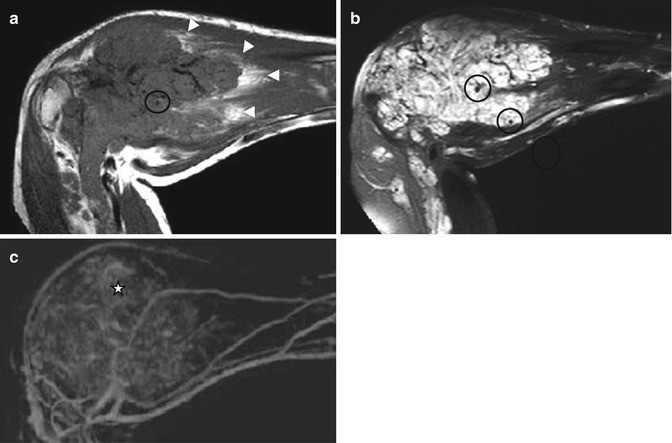

Intramuscular venous malformation of the upper extremity. (a) Sagittal T1-weighted MR image. (b) Sagittal T2-weighted image with fat saturation. (c) Maximum intensity projection (MIP) after 3D contrast-enhanced MR angiography, late venous phase. (a) T1-weighted image shows an intramuscular and extensive lesion which involves the forearm muscles and elbow joint, surrounded by fat component (arrowheads). (b) The lesion is composed of multiple tortuous hyperintense vessels on T2-weighted image representing a slow flow vascular malformation. At least two phleboliths (circles) are seen as low signal foci inside the dilated veins. (c) Late venous phase image from gadolinium-enhanced 3D MR angiography shows characteristic filing of cavernous spaces with diffuse and nodular enhancement (star)